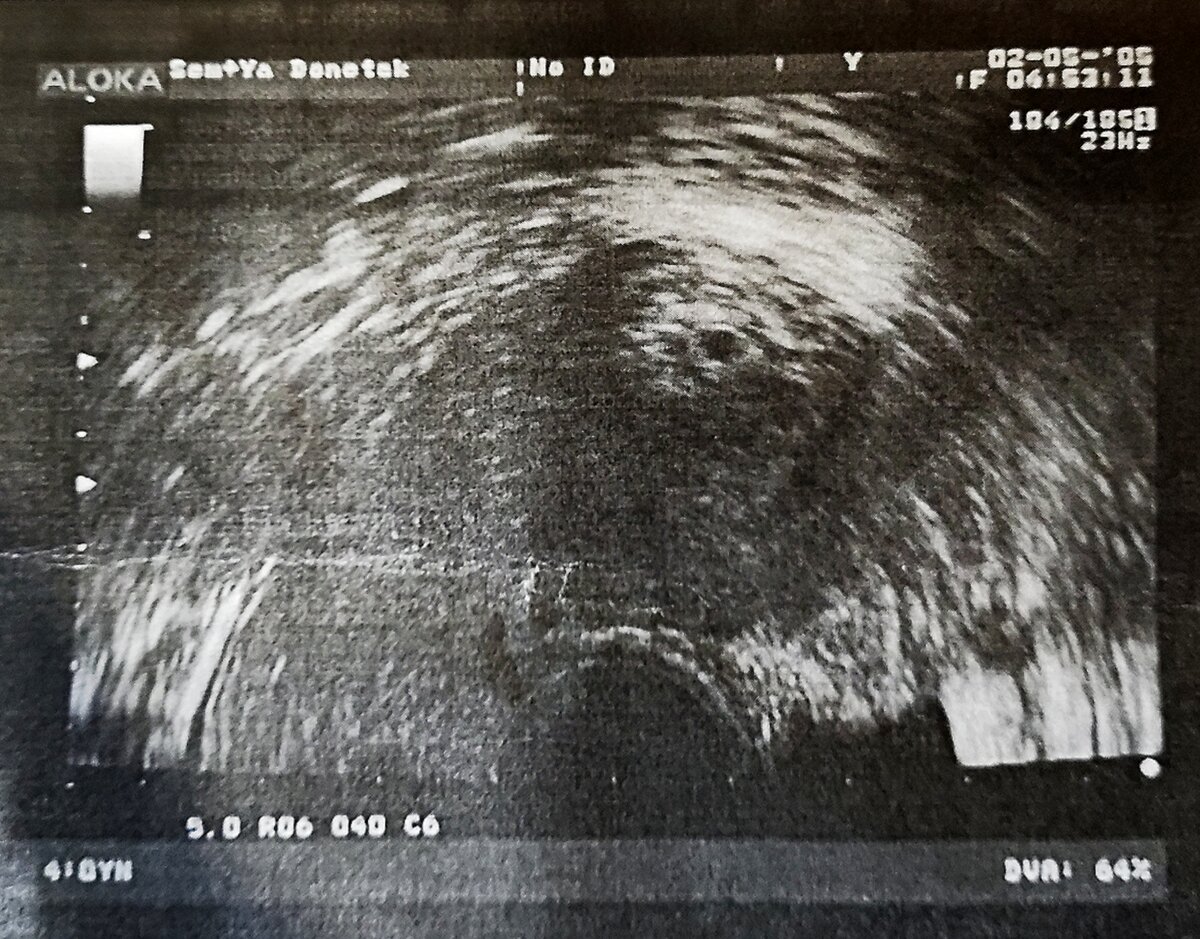

Мы приехали в больницу в назначенное время. Нас позвали, и мы вместе с мужем зашли в кабинет. В кабинете перед кушеткой был расположен большой экран, на котором уже через пару минут мы увидели нашего малыша. Правда, сам эмбрион ещё не было видно, но врач уверенно сказал: „Беременность малого срока, 5 недель, плодное яйцо в полости матки”.

В больнице нам выдали первую фотографию малыша, и в тот же вечер мы рассказали о беременности всем нашим родственникам.